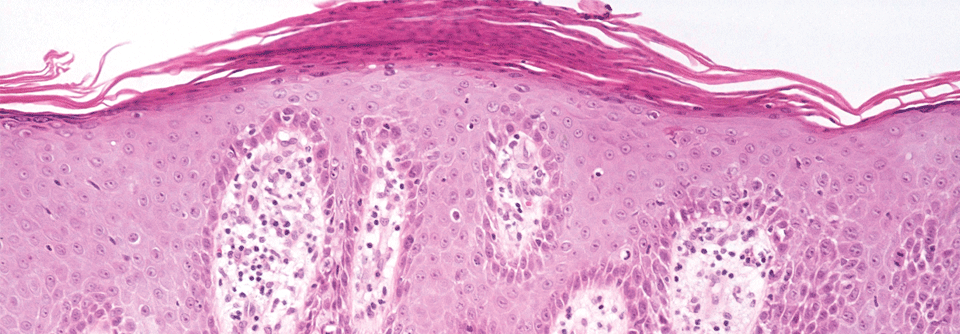

Essenziell ist die frühe Diagnose. Schon wenige Monate Verzögerung verschlechtern den Verlauf erheblich. Essenziell ist die frühe Diagnose. Schon wenige Monate Verzögerung verschlechtern den Verlauf erheblich. © wikimedia/James Heilman, MD